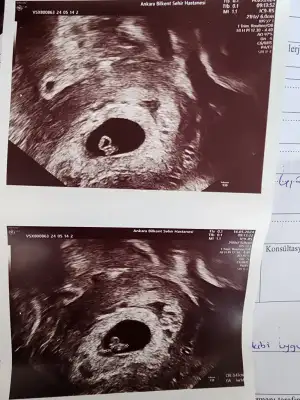

Canim merhaba geçmiş olsun farkli doktor gorusy al ve bende kendin düsürmeyi bekle ilk gebeligin ise genetik test yaptir 3 dusukle prof. Oldum 2si kürtajdjKızlar vajinal ultrason yaptı Dr smdi dış gebelik değilmiş şükürler olsun. Sağlıksız gebelik kesenin şekli bozuk dedi sadece kan sonucuma göre kürtaj yapacağını söyledi ama düzelme ihtimali vardır belki hemen kürtaj olmak istemiyorum ne yapacağımı bilmiyorum